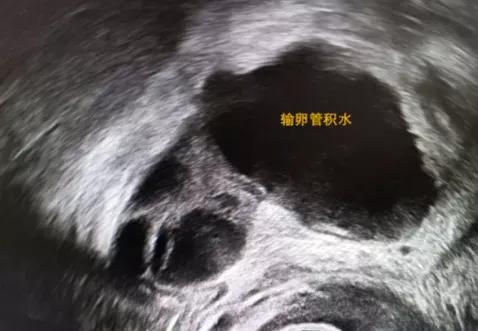

因输卵管因素接受IVF助孕的患者中有25%的女性存在B超可见的输卵管积水,研究发现 有输卵管积水者比没有输卵管积水者胚胎移植术后的临床妊娠率会降低50% ,同时会增加自然流产率。

(B超下输卵管积水)

其中 B超下发现输卵管积水者比未见者胚胎移植术后的妊娠率更低,即使是单侧积水也会降低妊娠率 。因为输卵管积水会影响胚胎着床,包括机械冲刷,输卵管积水会返流入宫腔影响胚胎着床;可能会干扰子宫内膜NF-κBp65的表达从而降低子宫内膜接受胚胎的能力,此外可能会产生IL-1等毒害胚胎的因子。 所以如果有积水,建议大家处理输卵管积水后再进行胚胎移植。